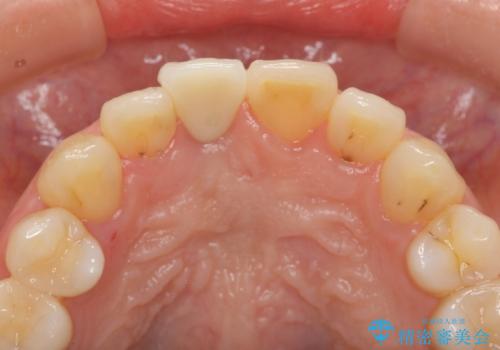

- 幼少期に前歯をぶつけて歯が折れ、神経の治療・クラウン治療を行った。グラつきと見た目の改善を希望して来院されました。

精密な仮歯をいれ、歯周組織を整えるとともにファイバーコア築盛、シェードテイキングを行い見た目に自然なジルコニアクラウンを製作していきます。